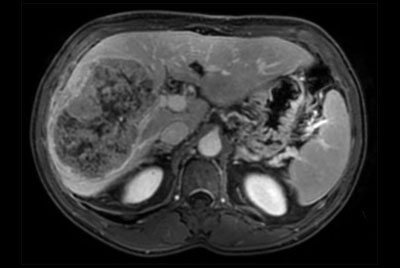

SmartSpeed Liver

Liver metastasis

Liver metastasis – Free breathing

Liver hemangioma with Compressed SENSE

Comprehensive Liver exam of focal liver lesions

Comprehensive Liver imaging at 3.0T

Comprehensive Liver imaging at 1.5T